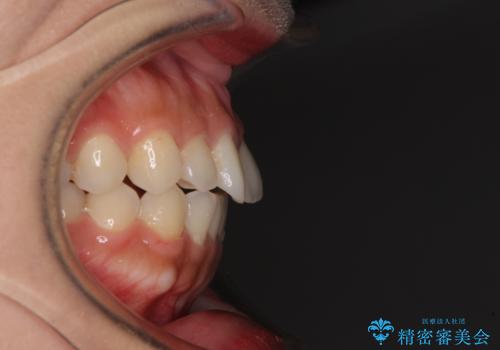

- 上顎前歯の叢生を気にして来院された患者様です。

下顎前歯や上下奥歯の咬み合わせには殆ど問題がないため、上顎前歯のみを矯正する治療を提案しました。

ワイヤー装置でもインビザラインでも可能でしたが、前歯のみをきれいに排列するのであればインビザラインの方が仕上がりが良いので、インビザライン・ライトにて治療を行うこととしました。